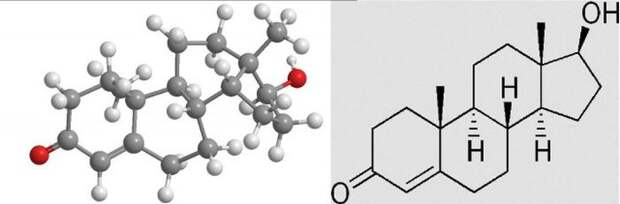

Во время влюбленности уровень тестостерона (мужского полового гормона, имеющегося в небольших количествах и у женщин) у мужчин снижается, а у женщин, наоборот, возрастает.